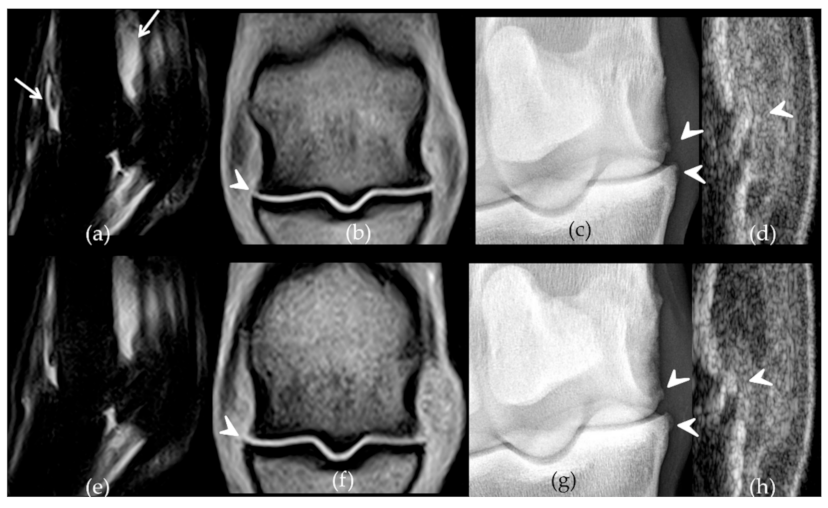

2.2. Follow-Up with Imaging Techniques

- Bertoni, L.; Jacquet-Guibon, S.; Branly, T.; Legendre, F.; Desancé, M.; Mespoulhes, C.; Melin, M.; Hartmann, D.-J.; Schmutz, A.; Denoix, J.-M.; et al. An Experimentally Induced Osteoarthritis Model in Horses Performed on Both Metacarpophalangeal and Metatarsophalangeal Joints: Technical, Clinical, Imaging, Biochemical, Macroscopic and Microscopic Characterization. PLoS ONE 2020, 15, e0235251. [Google Scholar] [CrossRef]